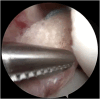

Graft-tunnel mismatch (GTM) is a known technical challenge that can occur with anterior cruciate ligament reconstruction when using a patellar tendon autograft. Two-incision anterior cruciate ligament reconstruction is a well-established technique with excellent outcomes and can serve as an excellent tool to prevent GTM. Traditionally, 2-incision femoral tunnel drilling has been performed using an over-the-top guide through a lateral incision, but more modern retrograde reamer guides can allow this to be done percutaneously. We detail how a minimally invasive 2-incision femoral tunnel drilling technique can be used in patients with patellar tendon lengths that are longer than average to avoid GTM.